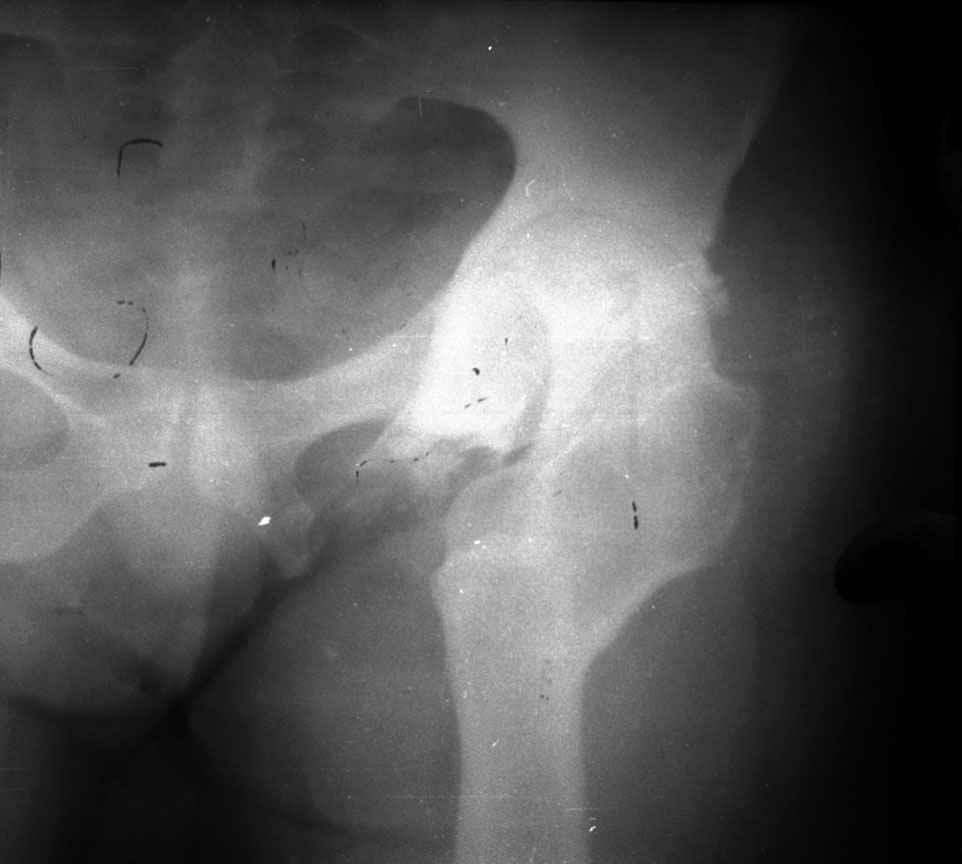

остеотомии. Я представил Р-граммы больных с неудачными р-ми после остеотомий.

Эндопротезирование у них было на порядок сложнее в отличие от артропластики без проведения остеотомии.

.........наверное не повезло. Но иногда это выход и очень хороший. М., 21 года спрыгнул в Армии с машины с исходом в гнойный коксит, свищевой формой в течении 1,5 лет. Операция проведена в 1988 году. результат хороший и сейчас и мы с пациентом хорошие приятели (Рентг-гр и фото прилагаю).

Вы немножко не поняли предмета нашего разговора. На представленных Вами Р-граммах речь идет о вальгизирующих остеотомиях, скорее всего в

комбинации с разгибанием... Никто и не оспаривает полезность этих остеотомий, мой личный опыт свидетельствует о том, что даже при

выраженной стадии коксартроза у лиц молодого возраста существенно снижается болевой с-м, ремиссия иногда достигает 12-16 лет, а там уже не

грех и протез поставить.

На обсуждение поставлен вопрос об эффективности опорной остеотомии по Илизарову (как правило), при врожденных вывихах бедра. Почувствуйте разницу...